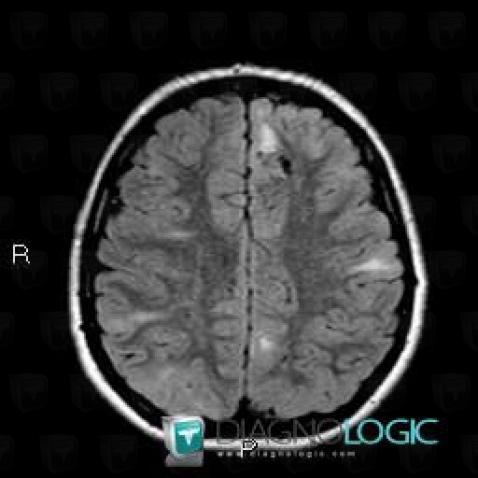

Here is the specific information in the key image above:

- Diagnosis Tuberous sclerosis, Location(s) Ventricles / Periventricular region, with gamuts

- Diagnosis Hamartoma, Location(s) Ventricles / Periventricular region, with gamuts Periventricular anomaly seen in MRI, Ventricular wall nodules

Here is the specific information in the key image above:

- Diagnosis Hamartoma, Location(s) Basal ganglia and capsule, with gamuts Basal ganglia T2W or FLAIR hypointense lesion

- Diagnosis Tuberous sclerosis, Location(s) Basal ganglia and capsule, with gamuts

Here is the specific information in the key image above:

- Diagnosis Tuberous sclerosis, Location(s) Corpus callosum, with gamuts Corpus callosum lesion

Here is the specific information in the key image above:

- Diagnosis Tuberous sclerosis, Location(s) Corpus callosum, with gamuts Corpus callosum lesion

Here is the specific information in the key image above:

- Diagnosis Hamartoma, Location(s) Basal ganglia and capsule, with gamuts Basal ganglia T2W or FLAIR hypointense lesion

- Diagnosis Tuberous sclerosis, Location(s) Basal ganglia and capsule, with gamuts